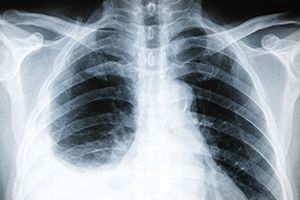

Плеврит

Плеврит — воспалительный процесс на серозной оболочке легких. Болезнь развивается в нескольких направлениях, когда плевральные лепестки выпадают на фибрильную поверхность, или скапливается гнойное отделяемое в полости плевры.

• рентгенологическое исследование грудной клетки;